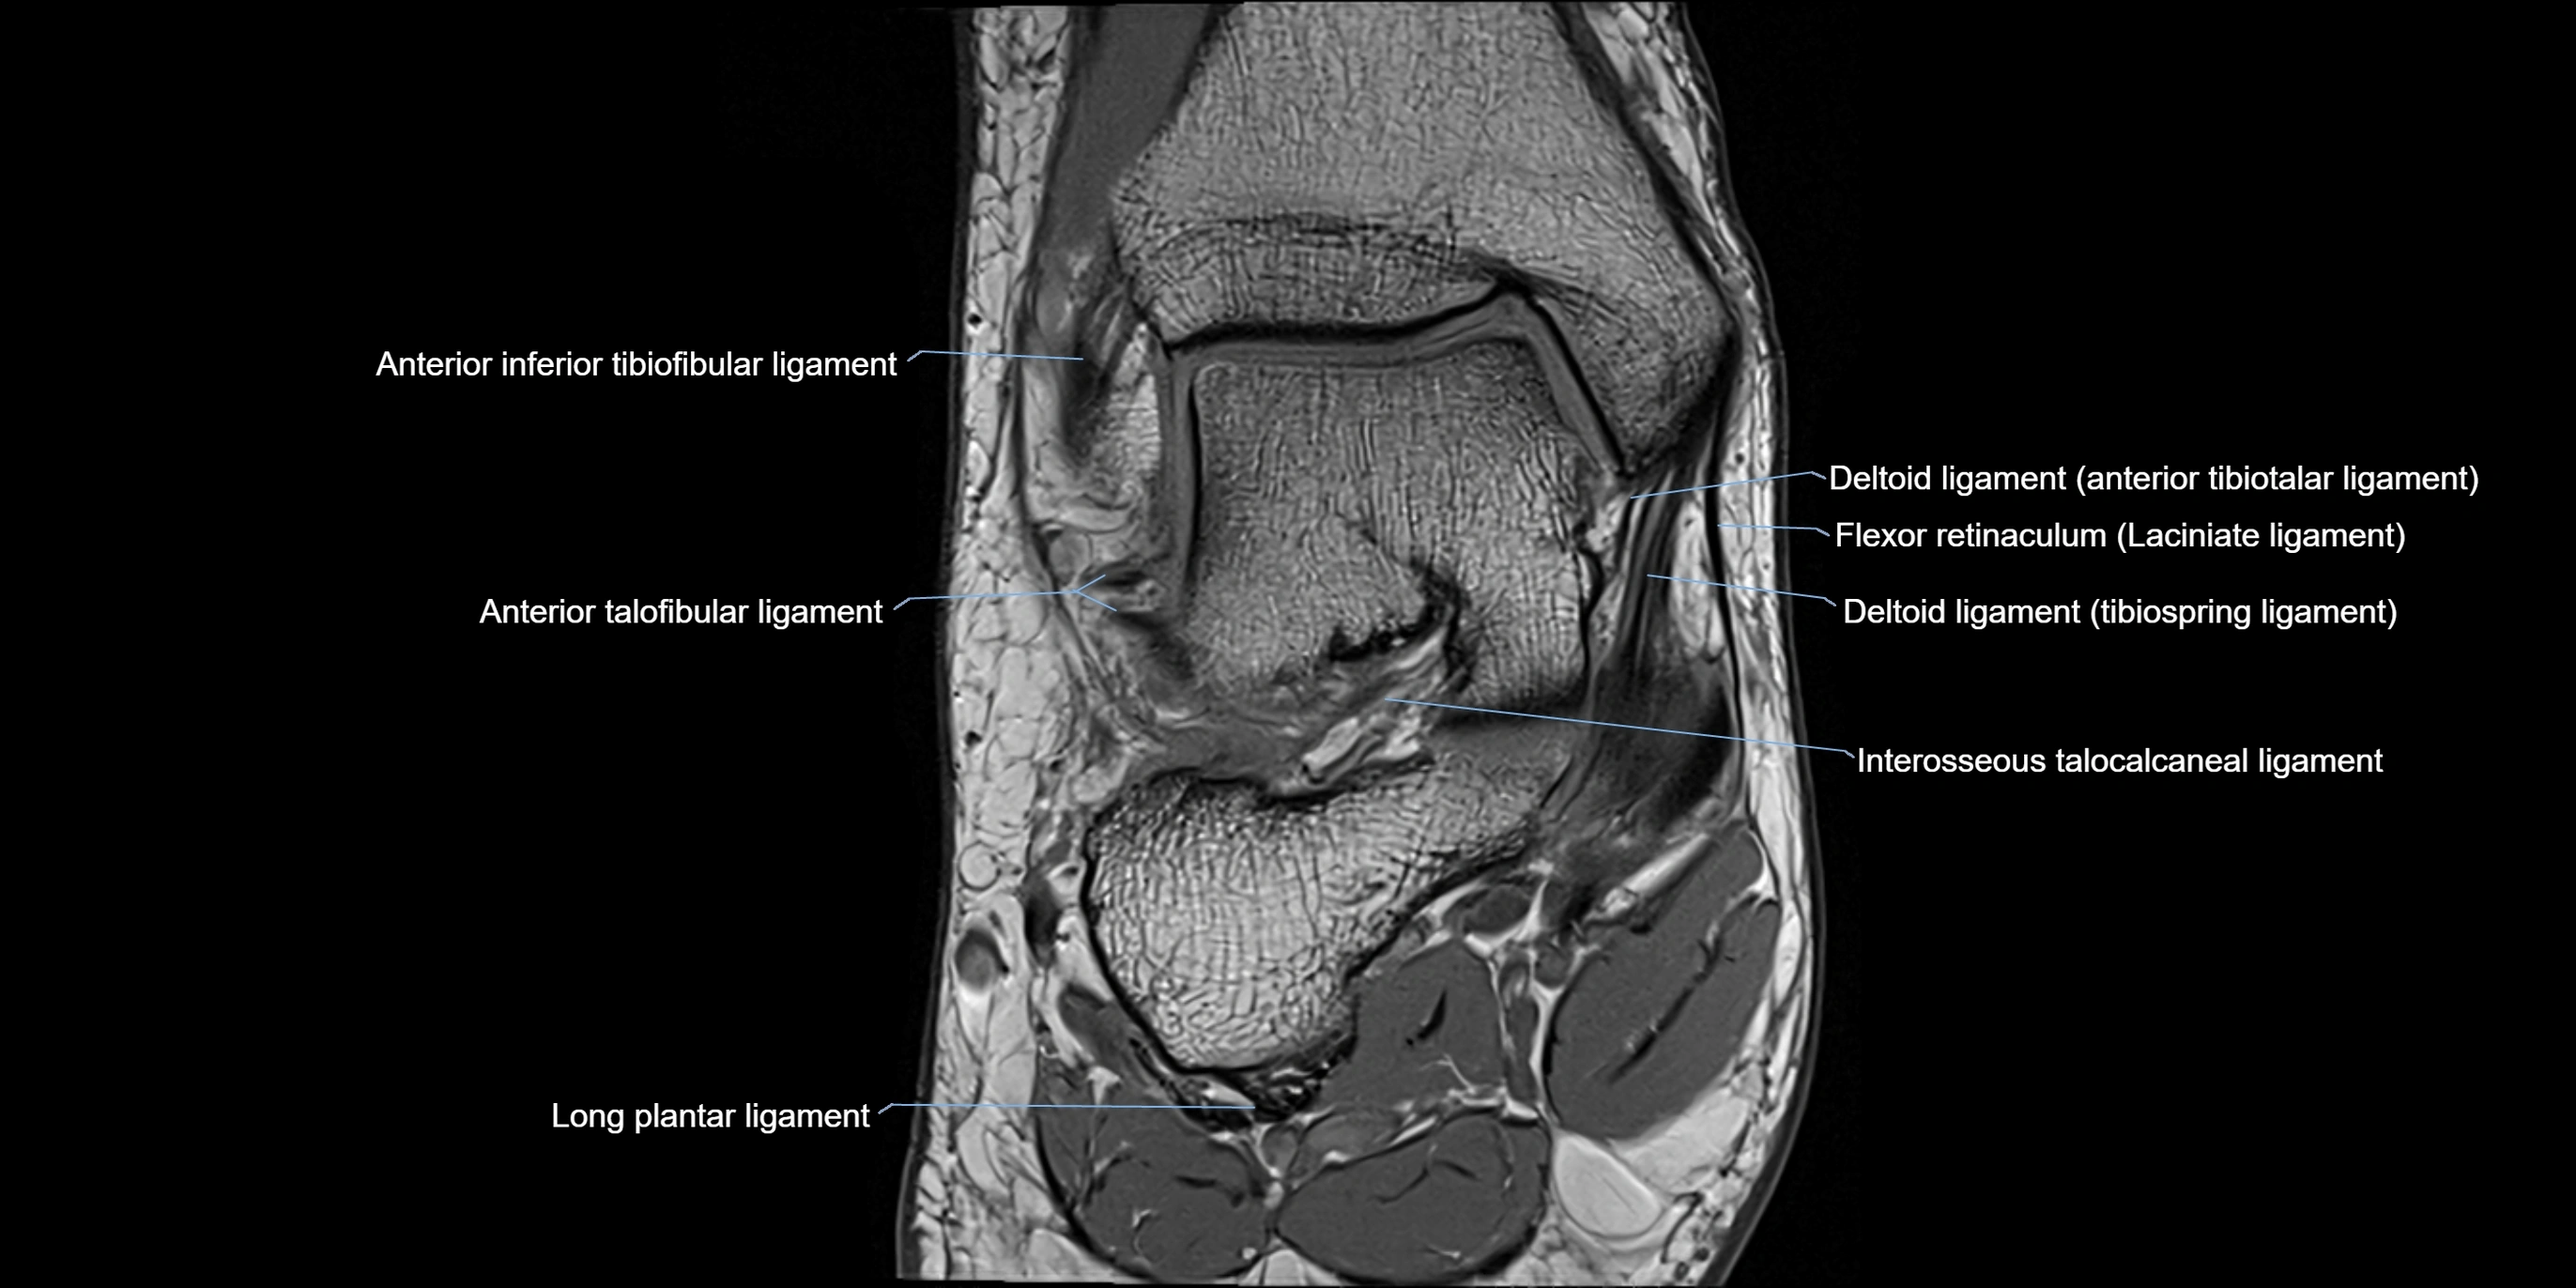

MRI image

image